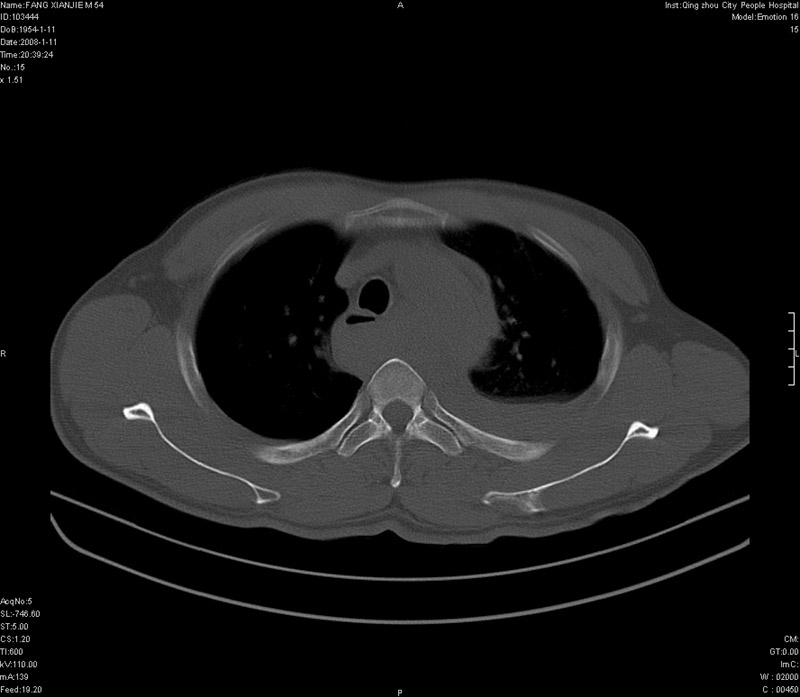

男性,40岁。胸部被车压伤伴胸痛1小时来院就诊。检查:一般情况尚可,血压110/80,胸部及上腹部压痛。结果在三天后公布。骨窗在横断位、冠矢状显示肋骨、胸椎、和胸骨未见骨折征象。

ct11308:胸部外伤1小时(证实病例) (2008-1-13 16:2)结果如下:病人入院后两小时后症状加重,8小时后在征得病人家属同意做了ct增强扫描。如下图。最终临床诊断:外伤性胸主动脉破裂并纵隔内血肿。由于有运动性伪影,胸骨在矢状面重建的图像似有骨折征,这是一种假象,我们称之为“假骨折”,这在多层ct重建中经常性遇到,必要时要结合横断图像鉴别之。现在,病人的一般情况较差,是否要手术家属尚有争议,如果手术修补,难度较大,需要专门预定制作固定支架。

当然,对于该病例,其它非重要的诊断还有:右侧少量气胸;左侧胸腔积液;左侧轻度肺挫裂伤。对于纵隔内血肿,我们曾经遇到过多例,也有怀疑主动脉的破裂,但是,均未得到具体出血部位的明确诊断。